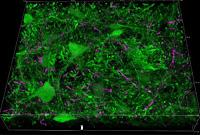

Los científicos de la Universidad de Massachusetts Amherst utilizaron la optogenética para identificar qué circuitos y qué partes del cerebro estaban involucradas en la PPI y si esta conexión entre la amígdala y el tallo cerebral era importante para la inhibición del sobresalto. Para detallar mejor esta conexión,utilizaron la electrofisiología junto con la optogenética para registrar la actividad eléctrica de neuronas individuales tomadas de secciones delgadas del cerebro, in vitro.